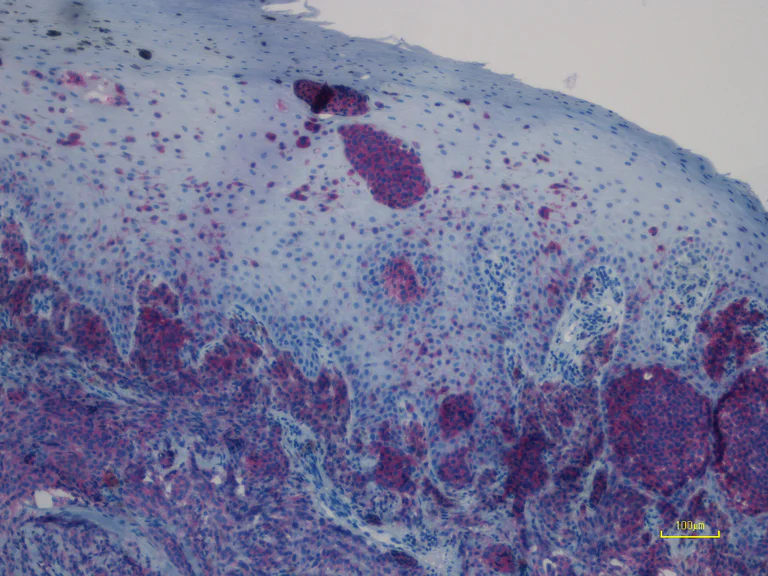

Immunohistochemical analysis of paraffin-embedded human primary malignant melanoma tissue (mutation status : NRAS Q61R) labeling NRAS with ab227658 at 1/100 dilution for 30 min at RT. The tissue was counterstained with Hematoxylin. Heat mediated antigen retrieval was achieved by using EDTA buffer pH 9.0 before IHC staining.

This image is courtesy of an anonymous collaborator.